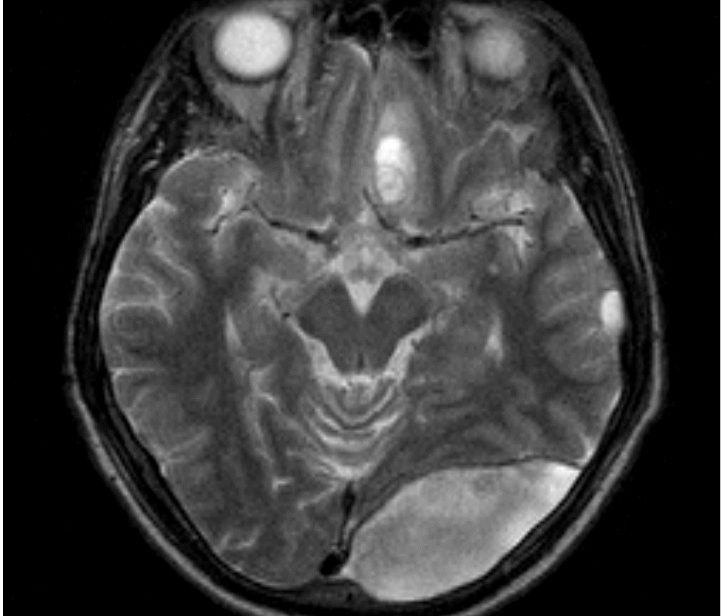

Для получения полной информации о состоянии головы можно использовать магнитно-резонансную томографию (МРТ), компьютерную томографию (КТ) или рентген. Ангиография поможет оценить состояние сосудов. Все собранные данные позволяют определить тип кровоизлияния, размеры гематомы, её локализацию и выявить возможные повреждения основания черепа.